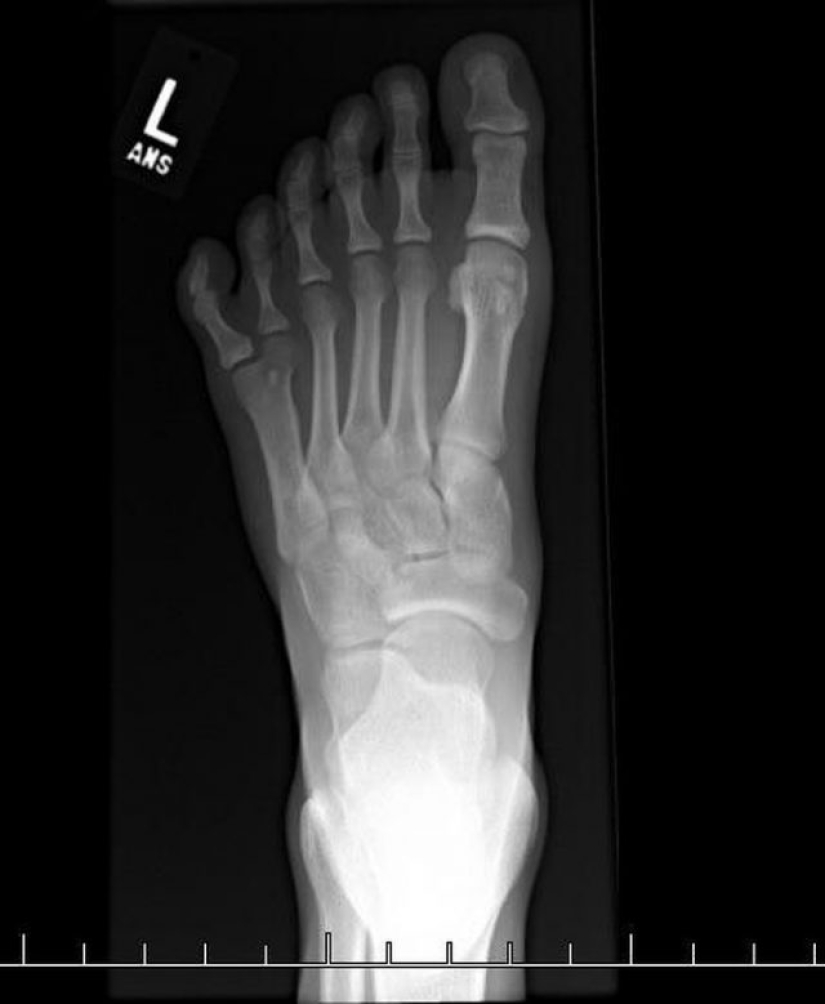

7. X-ray showing 6 fingers.